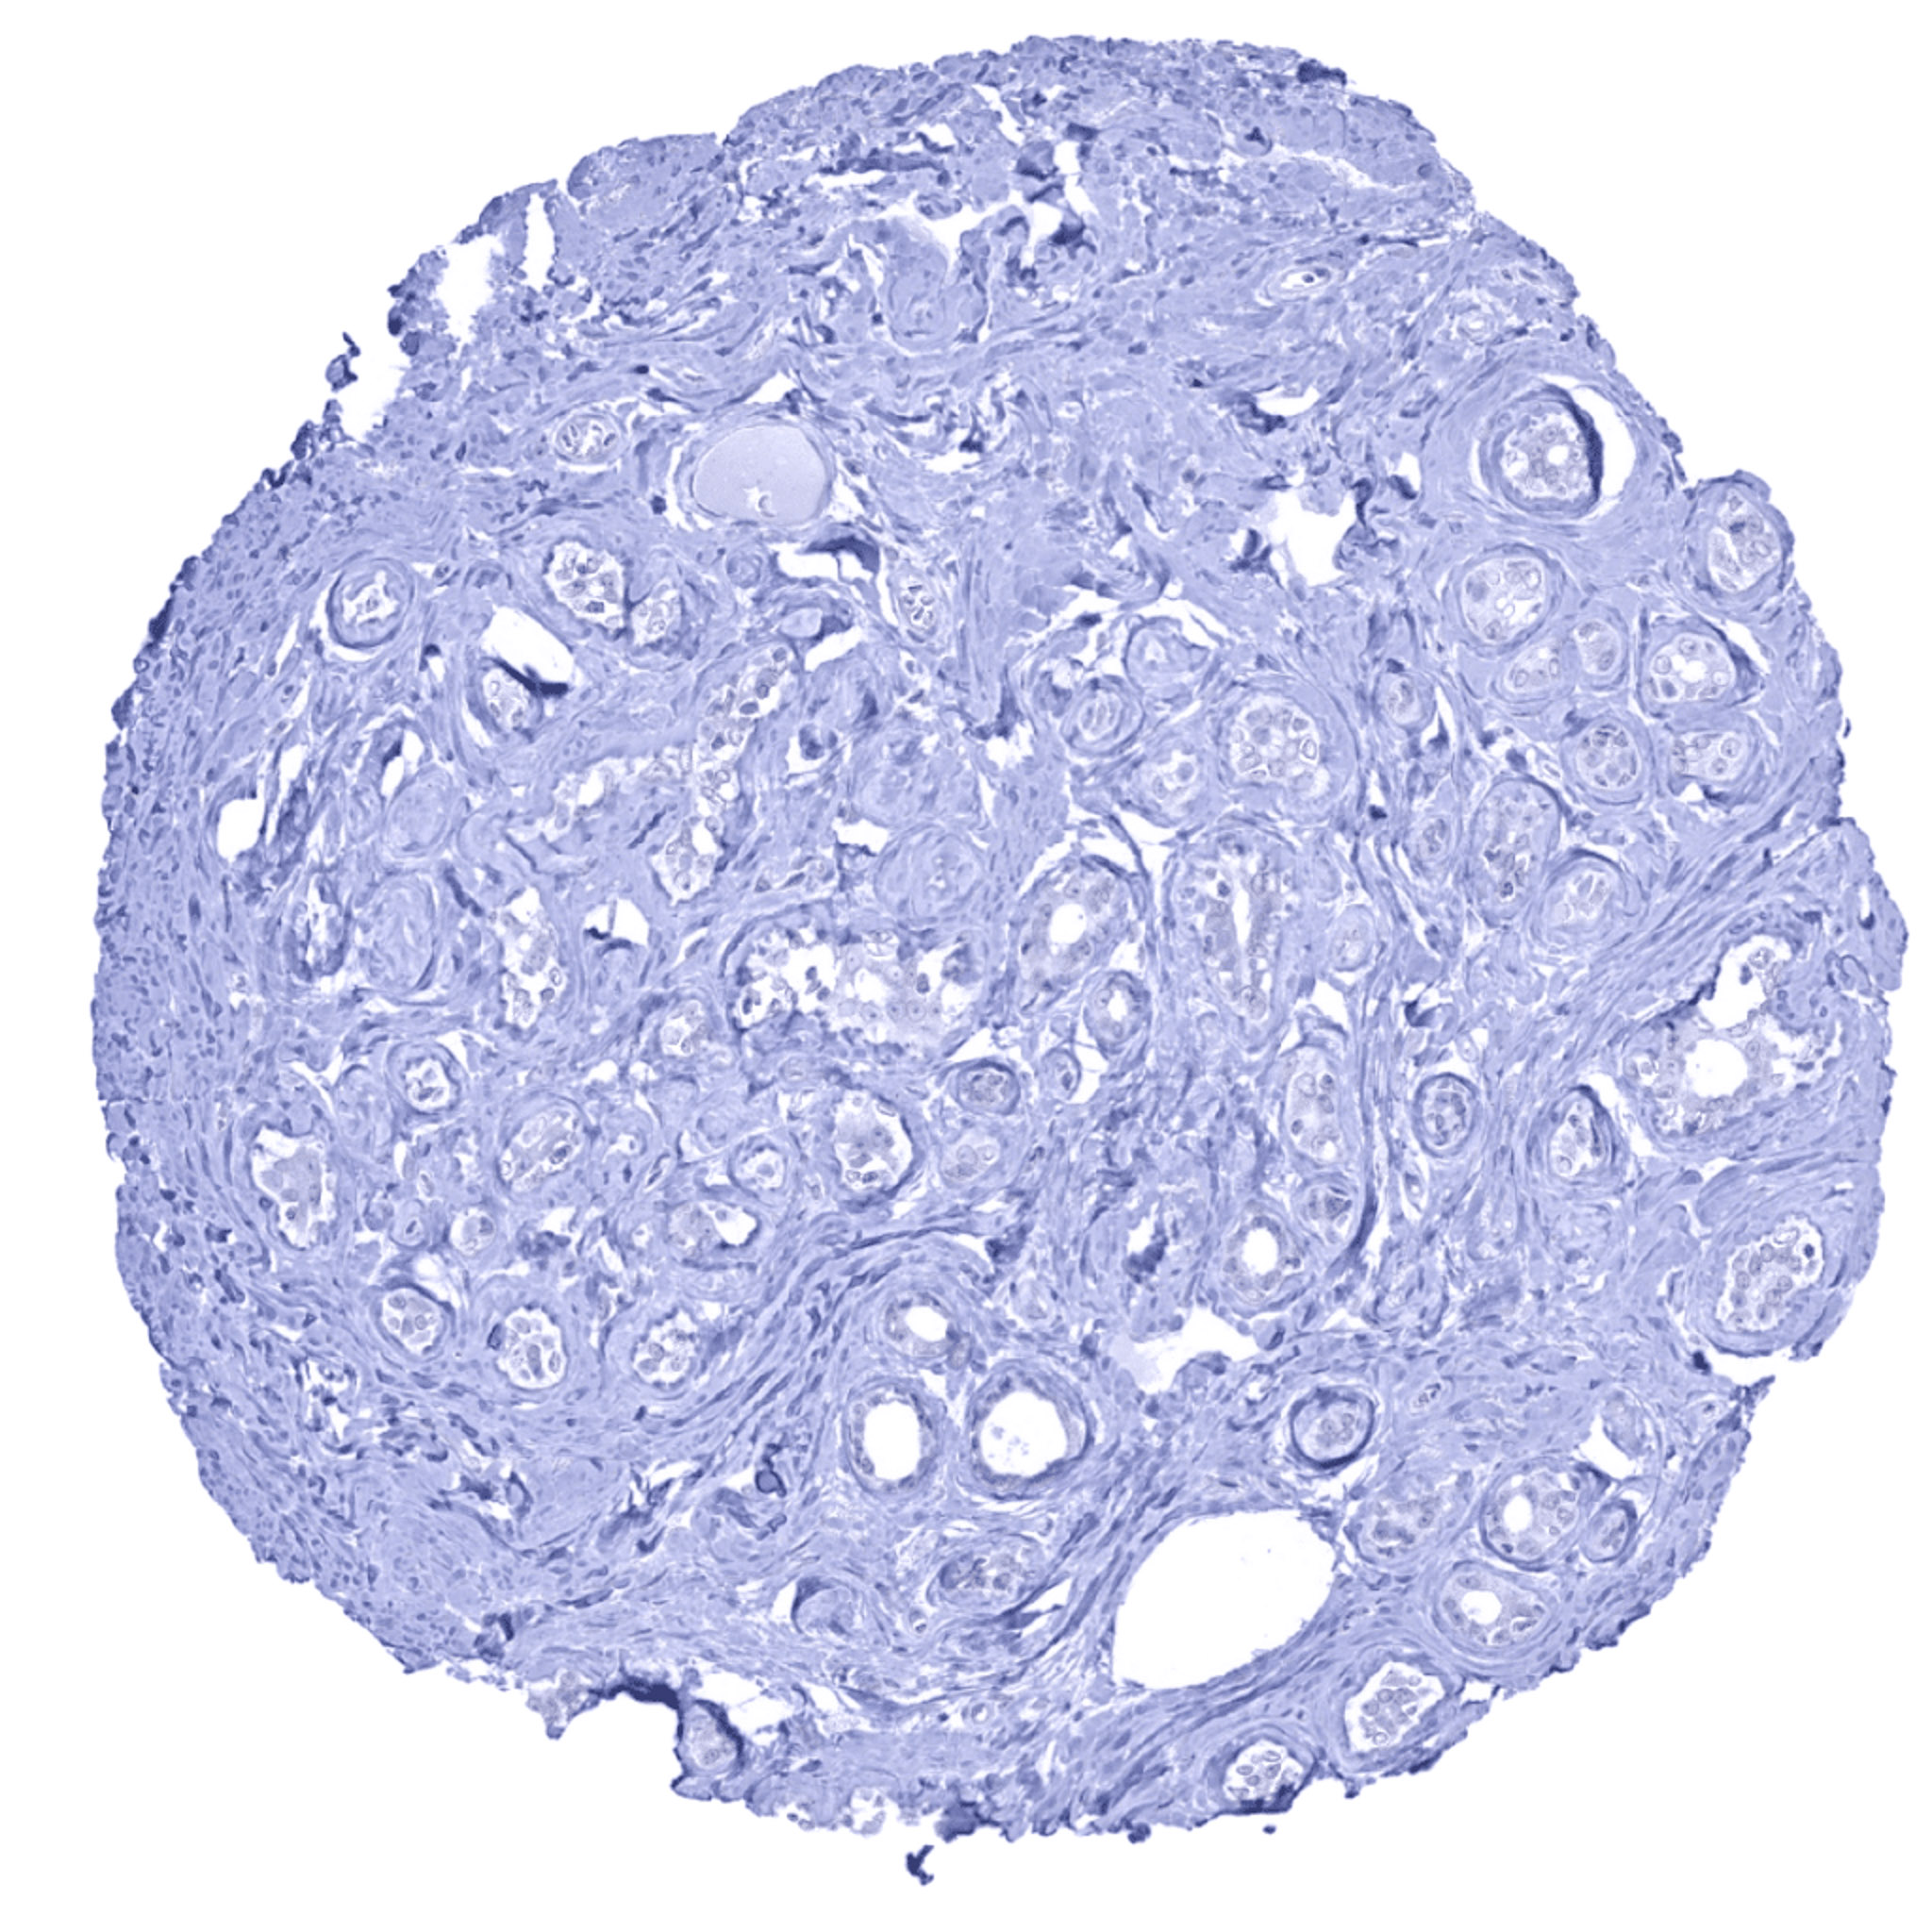

Urinary bladder, urothelium – Strong UPK1B staining in suprabasal urothelial cells